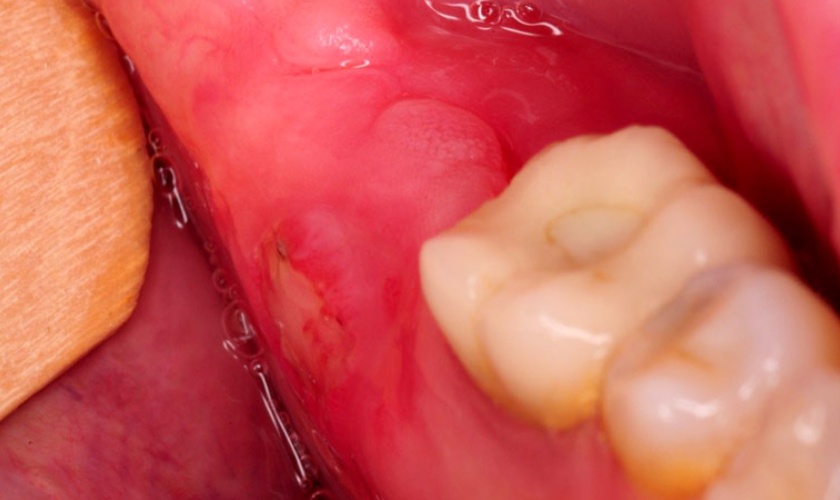

– Sưng tấy, viêm nhiễm: Khi răng khôn mọc lên bị viêm hoặc mọc kẹt, vùng nướu xung quanh thường bị sưng đỏ, nóng rát, có thể xuất hiện mủ hoặc hạch vùng cổ. Nếu không xử lý sớm, tình trạng này có thể lan sang các mô mềm quanh hàm, gây nhiễm trùng nghiêm trọng.